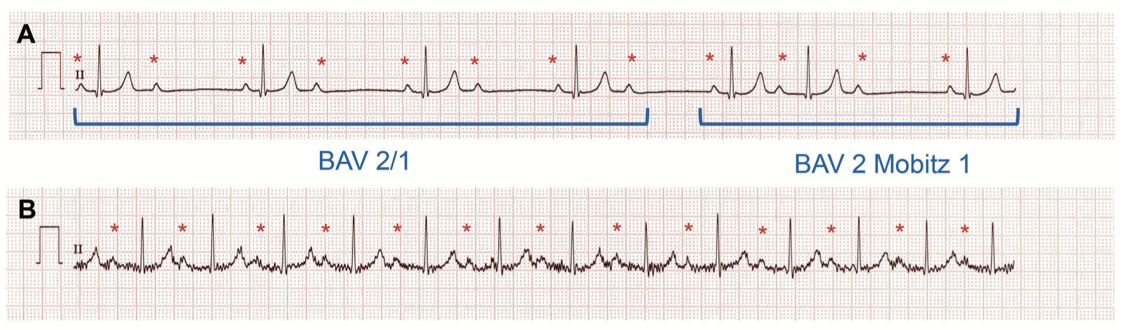

Figure 3. Trouble conductif partiel.

A : bloc auriculoventriculaire (BAV) type 2. Le BAV est 2/1 sur les 4 premiers battements avec 1 onde P (*) sur 2 conduite. Sur les battements suivants, le PR s’allonge progressivement jusqu’à ce qu’une onde P soit bloquée (BAV 2 Mobitz 1).

B : tracé du même enfant, après quelques flexions (tracé artéfacté par le mouvement), chaque onde P est suivie d’un QRS. Le PR reste allongué (BAV 1).